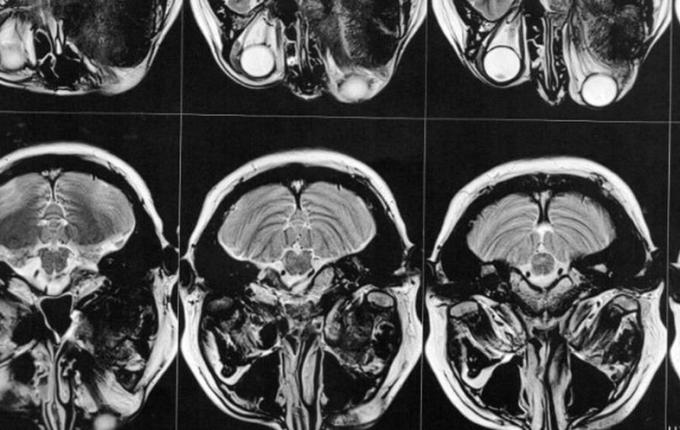

Então este médico solicitou exames de imagem (ressonância magnética e tomografia) para avaliar a situação, os quais foi constatado que o meningioma ainda está ali, e que continua empurrando o olho e se expandindo para outras áreas. Trata-se de um meningioma gigante (medindo 6 x 6,6 x 6 cm), que está localizado na placa do assoalho da fossa média e anterior.